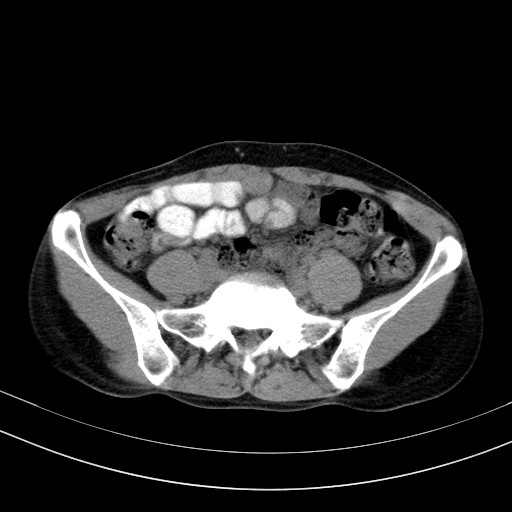

以下是引用卜一在2009-4-7 5:08:00的发言:[br]宫颈癌可能。支持!

以下是引用随光逐影在2009-4-7 8:17:00的发言:[br]考虑宫颈占位性病变(宫颈癌?);建议行进一步检查。

以下是引用jiangjing在2009-4-7 16:46:00的发言:[br]宫颈增大,结构不清,右侧附件区可疑囊样占位,建议增强及mri 检查